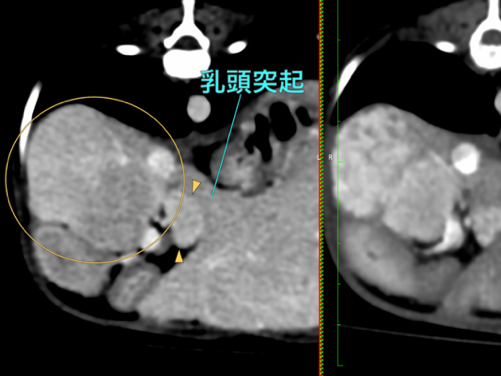

他院にて肝酵素の上昇および肝臓の結節性病変を指摘され、精査および治療のため当院に紹介来院となりました。右肝区域(W39 x L45 x H30mm)、尾状葉乳頭突起(W11 x L16 x H13mm)、内側左葉吻側領域、内側/外側左葉では、結節/腫瘤様の所見を複数認められ最大は外側左葉領域に40mm大の腫瘤が認められました。 本症例は、肝臓内の複数箇所に腫瘤性病変を有し、かつ高齢であることから、全身状態への負担を考慮し、右側および左側に対して2回に分けて肝動脈塞栓術を実施する方針としました。初回の処置として、右肝区域の腫瘤に対する動脈塞栓術を実施し、術後は大きな合併症もなく経過し、術後2日目に退院となりました。

手術前のCT検査での評価